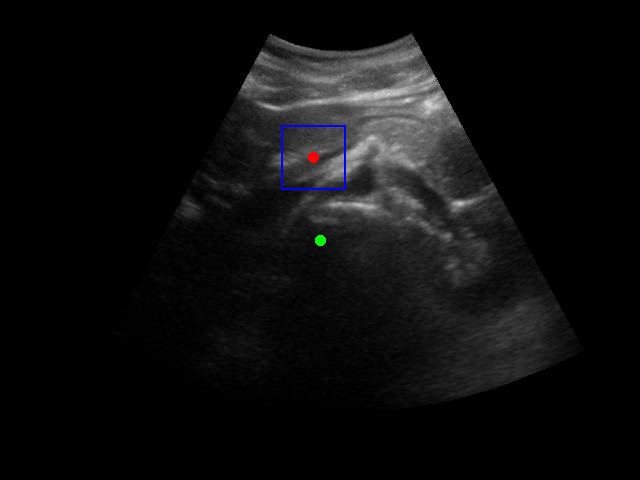

Segmentation Example Segmentation Example Segmentation Example

Example of segmentation results on an abdominal ultrasound image. The top left in the above is the orginal cropped image of the Ultrasound , the top right shows the mask_cropped image after the segmentation . Then combining these two we get our overalled_cropped image where the red overlay shows the segmented region of interest.